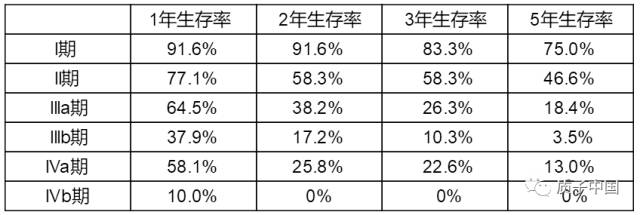

1、Ⅰa、部分Ⅰb期肝癌患者,如无手术切除或消融治疗适应证或不愿接受有创治疗,可以酌情考虑采用SBRT作为治疗手段。

2、Ⅱa、Ⅱb期肝癌患者,TACE联合外放射治疗,可以改善局部控制率、延长生存时间,较单用TACE、索拉非尼或TACE联合索拉非尼治疗的疗效好。

3、Ⅲa期肝癌患者,可以切除伴门静脉癌栓的肝癌行术前新辅助放射治疗或术后辅助放射治疗,延长生存;对于不能手术切除的,可以行姑息性放射治疗,或行放射治疗与TACE等联合治疗,延长患者生存。

4、Ⅲb期肝癌患者,部分寡转移灶者,可以行SBRT,延长生存时间;淋巴结、肺、骨、脑或肾上腺等转移灶,外放射治疗可以减轻转移灶相关疼痛、梗阻或出血等症状,延长生存时间。

5、一部分无法通过手术切除的肝癌患者,肿瘤经放射治疗后缩小或降期,可以转化为手术切除。

6、肝癌术后病理示有脉管侵犯者、肝癌手术切缘距肿瘤≤1cm的窄切缘者,术后辅助放射治疗可以减少病灶局部复发或远处转移,延长患者无瘤生存期。

7、外放射治疗也可以用于等待肝癌肝移植术前的桥接治疗。hvT帝国网站管理系统